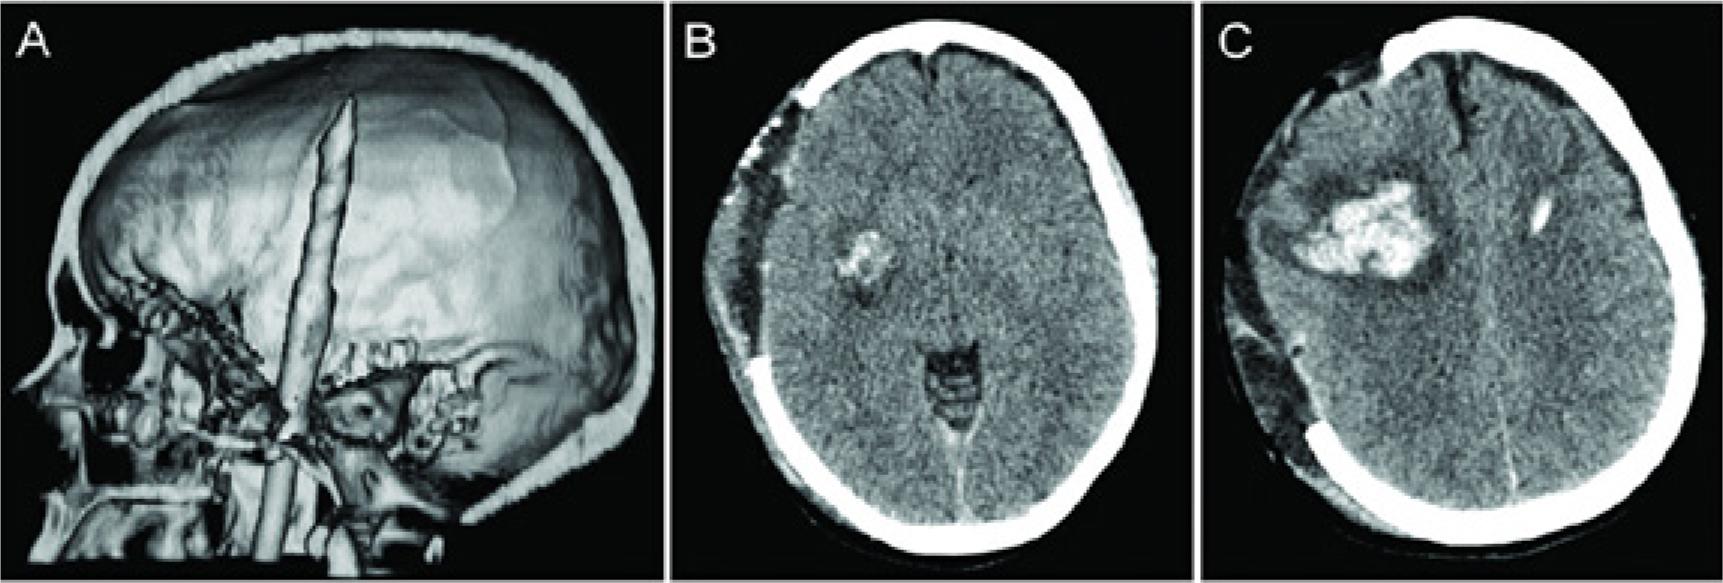

| Acioly et al., 2017 | 28, F | Left | Unilateral Penetrating Spear gun injury | Right operculo-insular hematoma (day 1) | Automatic-voluntary dissociation Loss of voluntary control of muscles innervated by cranial nerves V, VI, VII, IX, X, and XII | Decompressive craniectomy SLT | Full recovery (24mo) |